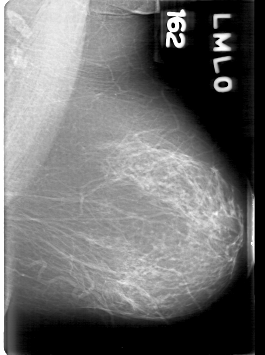

D_4094_1.RIGHT_MLO

RIGHT_MLO LINES 5311 PIXELS_PER_LINE 3706 BITS_PER_PIXEL 12 RESOLUTION 43.5 OVERLAY